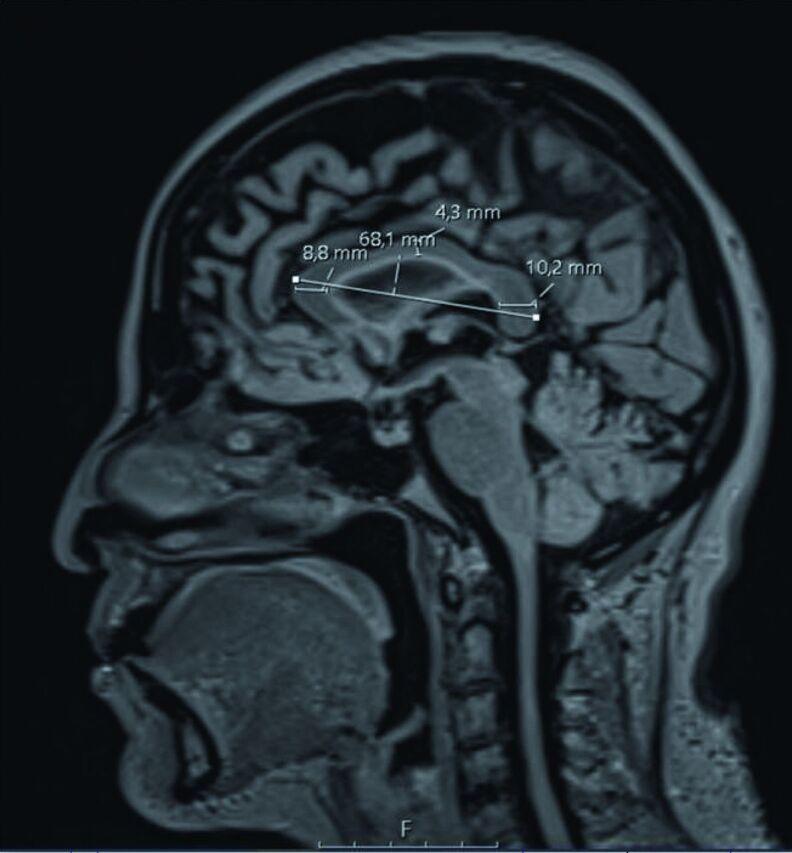

In this study, 150 MS patients (disease duration 12.6±5.9 years) and 150 healthy control subjects were scanned. Corpus callosum index was manually measured from the mid-sagittal slices on MRI. A deep learning architecture-based U-Net model was used for automatic corpus callosum segmentation from 2D brain MRI.

在本研究中,对150例MS患者(病程12.6±5.9年)和150例健康对照者进行了扫描。从MRI的正中矢状位切片上手动测量胼胝体指数。使用基于深度学习架构的U-Net模型从二维脑MRI中自动分割胼胝体。